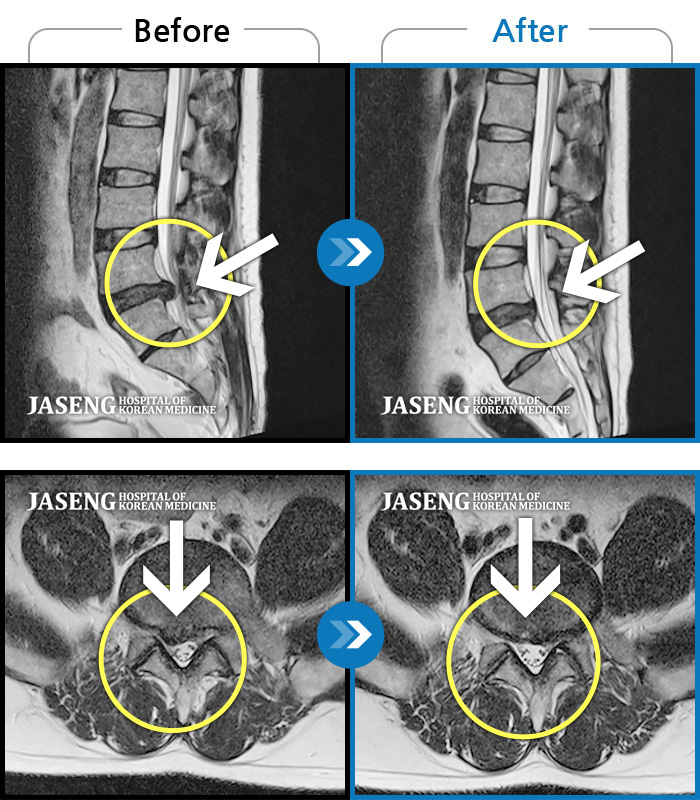

Before

After

환자에게 사전 동의를 받아 동일 조건에서 촬영되었습니다.

개인에 따라 치료 후 부작용이 발생할 수 있으니 의료진과 상담 후 치료를 진행하시기 바랍니다.

허리통증, 왼쪽 다리 통증 및 근력 저하

허리 통증과 좌측 다리 통증